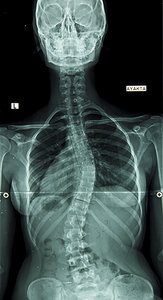

I recently came across an article on "adult scoliosis"1 in The New York Times. According to the article, this seems to be a newly recognized condition: adult-onset scoliosis, "an asymmetrical curvature of the spine that, if unchecked, could eventually lead to a shorter and more crooked disability by entrapped spinal nerves, and dependency on a walker to maintain balance."

Going back to the dustbins of my memory, I recall that a scoliosis is a lateral curvature of the spine – any lateral curve of the spine.2 If you tilt 1 degree to one side, that is a scoliosis. This is more regional and the curve is spread over several spinal levels.

Alternatively, the "disease" process of scoliosis is different in that the curve is a hard angulation at one spinal level, more than 30 degrees, and must be shown to be measurably increasing within a window of time. This process is most often seen in younger adolescents when the body is growing at a rapid rate.